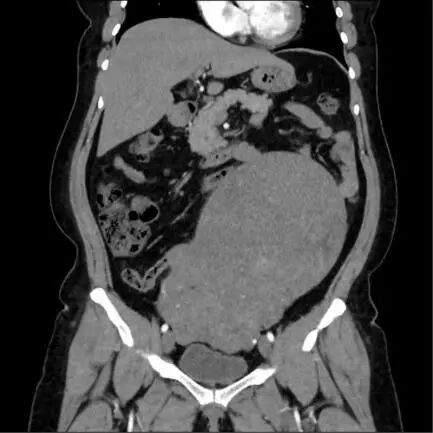

患者李女士(化名)曾于2015年因子宫肌瘤在外院接受腹腔镜下子宫肌瘤剔除术,术后因自觉恢复良好,未坚持定期复查。直至近期腹部受到轻微撞击后出现持续腹痛,才来潜江市中心医院就诊。经超声检查发现,其子宫形态失常,增大如孕7月大小,肌壁间可见多个大小不等的肌瘤样占位,其中最大者截面约110mm×90mm,因患者体型偏胖,此前并未察觉腹部异常,结合超声结果门诊医生建议尽快住院手术。

鉴于肿瘤体积巨大、生长速度不确定,且患者有肌瘤手术史,为排除子宫肉瘤等恶性病变可能,妇科主任周筠予以高度重视,迅速启动多学科会诊机制。结合影像学特征与临床指征进行综合评估,并制定了个体化的手术方案与应急预案,确保诊疗过程稳妥周全。

12月24日,在手术团队的精细操作与密切协作下,成功将病变子宫完整切除。术后病理检查进一步明确了诊断,排除恶性肿瘤可能,患者恢复情况良好。